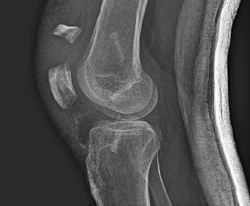

A las 2 semanas reinicia la fisioterapia. En septiembre de 2019, a los 2 meses de la cirugía, sufre una caída casual, presentando una fractura de la rótula derecha (Figura 3), por lo que se lleva a cabo una reducción abierta y osteosíntesis de la fractura en “T” de la rótula derecha. En la cirugía se realiza valoración artroscópica de la plastia del LCA, que se aprecia íntegra.

Figura 3. Imagen de la fractura de la rótula. Se aprecia la situación de las pastillas óseas en los túneles tibial y femoral.